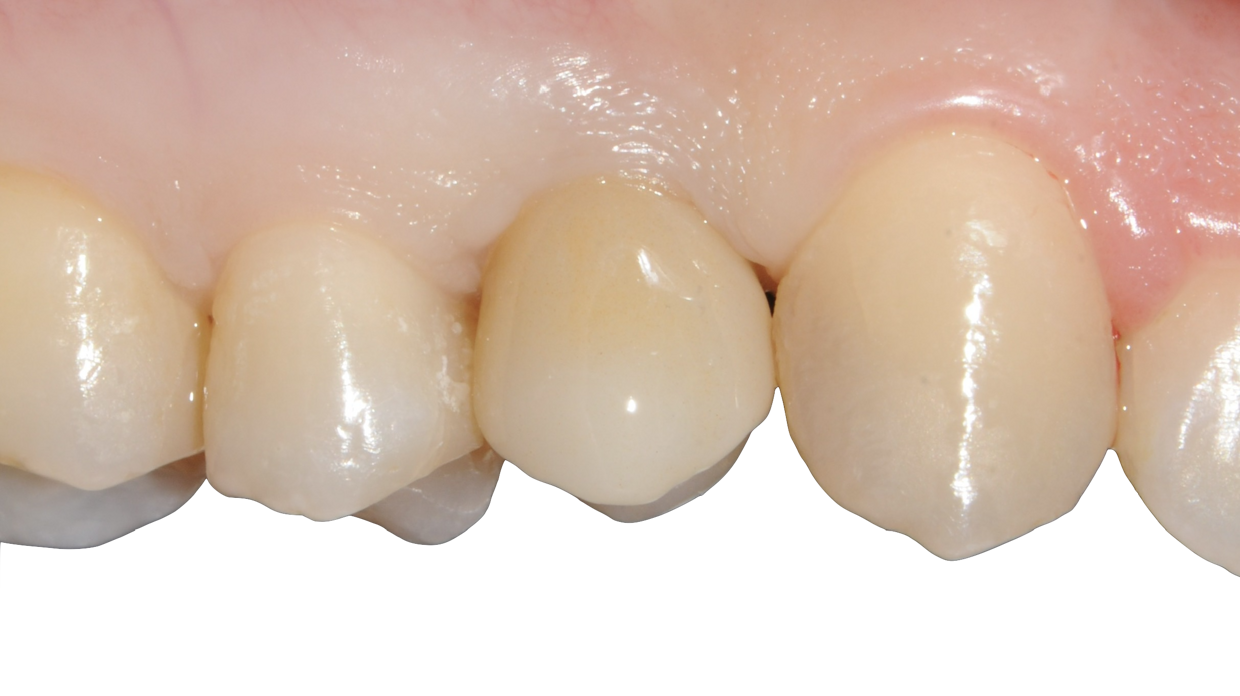

Impianto con tecnica Flapless

Minimamente invasivo, senza lembo chirurgico nè punti di sutura

Il posizionamento degli impianti è stato pianificato prima dell'intervento su un software dedicato. In un'unica seduta, dopo l'estrazione degli elementi dentari compromessi, sono stati immediatamente inseriti gli impianti nella posizione pianificata, grazie alla realizzazione della dima chirurgica. Per ridurre il riassorbimento osseo a lungo termine e garantire quindi una maggiore resa estetica (vista la zona d'intervento), la chirurgia è stata eseguita con una particolare tecnica denominata: Socket Shield Technique.